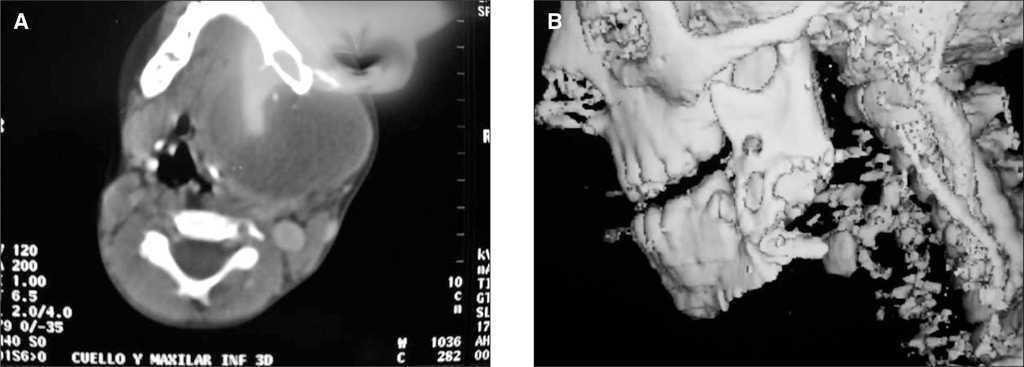

La tomografía computarizada (TC) realizada mostró una lesión de tejidos blandos que comprometía la hemimandíbula izquierda (fig. 2A y B). La biopsia de la lesión confirmó el diagnóstico de fibromixoma de origen odontogénico. Con este diagnóstico, se practicó resección completa macroscópica del tumor con reconstrucción con placa de mandíbula, por el servicio de cirugía plástica (fig. 3A y B).

Figura 2A y B. TC y reconstrucción.